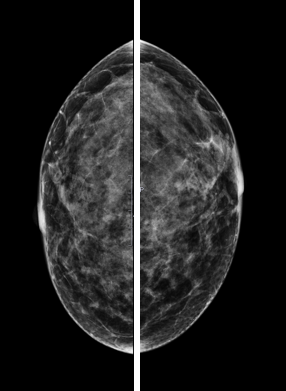

La mamografía actualmente es el método de imagen más utilizado tanto en el estudio de pacientes con síntomas mamarios como en pacientes asintomáticas, con el fin de diagnosticar el cáncer de mama en estadios iniciales. Es un método de imagen que conlleva radiación ionizante y necesita compresión de la mama para conseguir estudios de calidad. El estudio convencional consta de dos proyecciones de cada mama, una craneocaudal (CC) y otra oblicua medio lateral (OML). La realización de dos proyecciones en cada mama es fundamental para no pasar por alto lesiones visualizadas en una sola proyección, así como para realizar una correcta localización de estas.